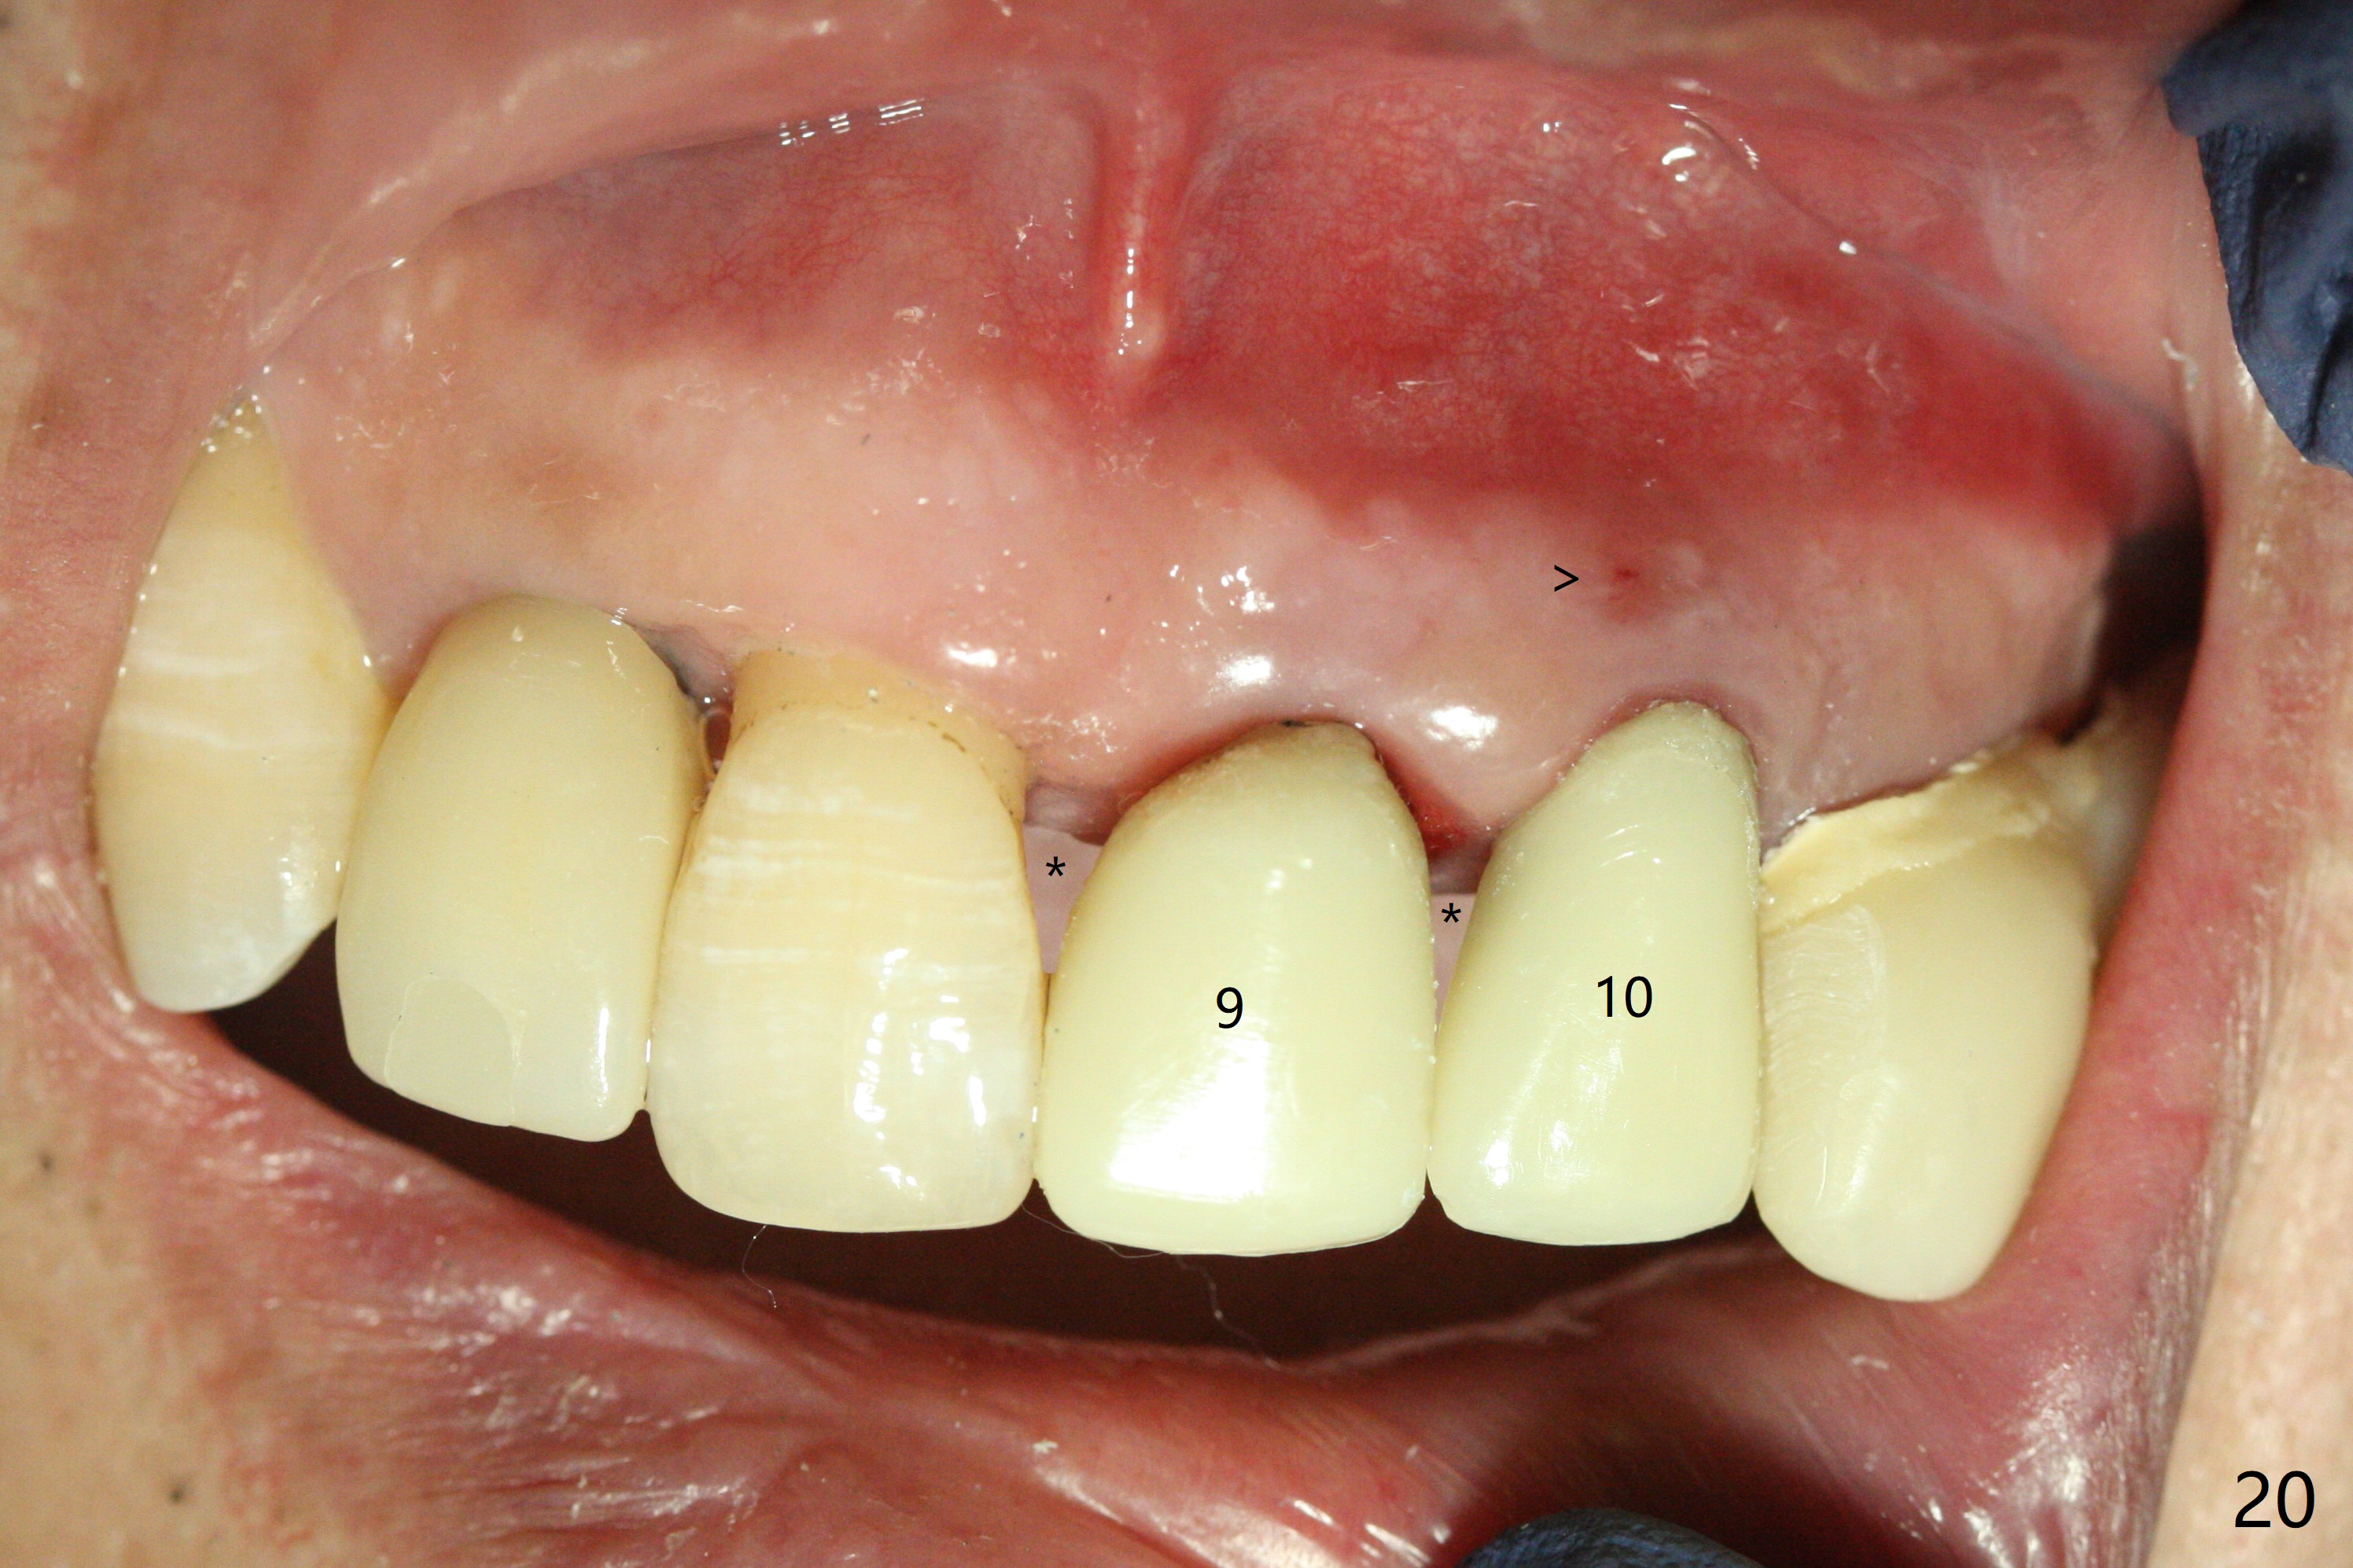

The patient returns 8 days postop, uncomfortable with overhang in the provisional (Fig.10 *). The sockets appear to be healing with loose bone graft (Fig.11) when the provisional is removed for trimming (Fig.12). Six (for #7,13) and seven (#9-11,15) months postop, the soft (Fig.13,17) and hard (Fig.14-16,18) tissues heal. It appears that the trajectory at #9,11 and 13 should be changed by using angled abutments (Fig.18,19 (panoramic X-ray taken 2 months earlier)) before provisional and final restoration.

In fact angled abutments are used at #11 and 13 (4.5x15 degree (5 mm)A) with a straight abutment at #15 (5.5x4(4) mm).

There is 1-2 thread exposure mesial and distal at #10 two years postop (Fig.20'), which may be related to the small fistula labially (Fig.20 >). It appears that the implant at #10 was placed too high (Fig.21) and labially (Fig.22). In fact the bridge fractures between #12 and 13 during pandemic.